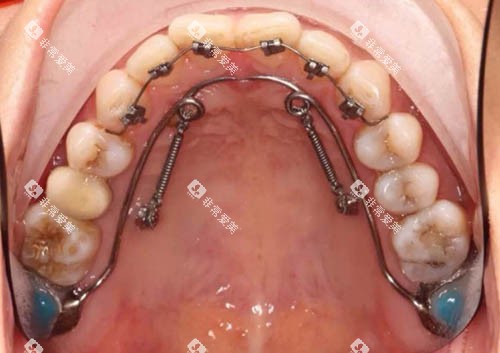

Ebrace舌侧矫正作为一种可靠的牙齿矫正技术,近年来受到了许多追求美观和个性化矫正方案患者的关注。它通过将矫治器安装在牙齿的内侧(舌侧),实现了高度的隐蔽性,几乎不影响外观。

高度隐蔽:矫治器安装在牙齿内侧,从外观上看几乎无法察觉,适合对美观要求较高的患者。

个性化定制:采用CAD/CAM技术和3D打印技术,根据患者的牙齿形态进行个性化设计,确保矫正结果和舒适度。